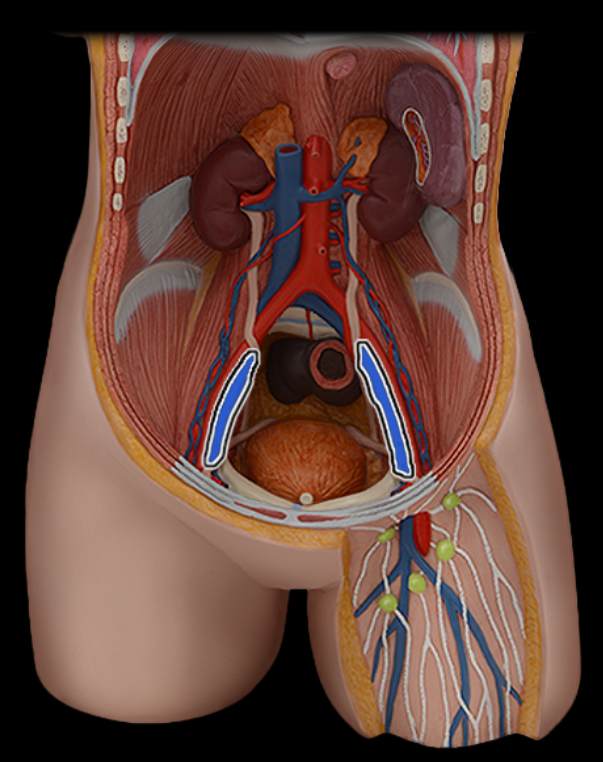

Abdominal aorta

Common iliac a.

Common iliac v.

External iliac a.

External iliac v.

Femoral a.

Femoral v.

Gonadal a.

Gonadal v.

Inferior vena cava

Lumbar a.

Lumbar v.

Renal a.

Renal v.

Superior mesenteric a.